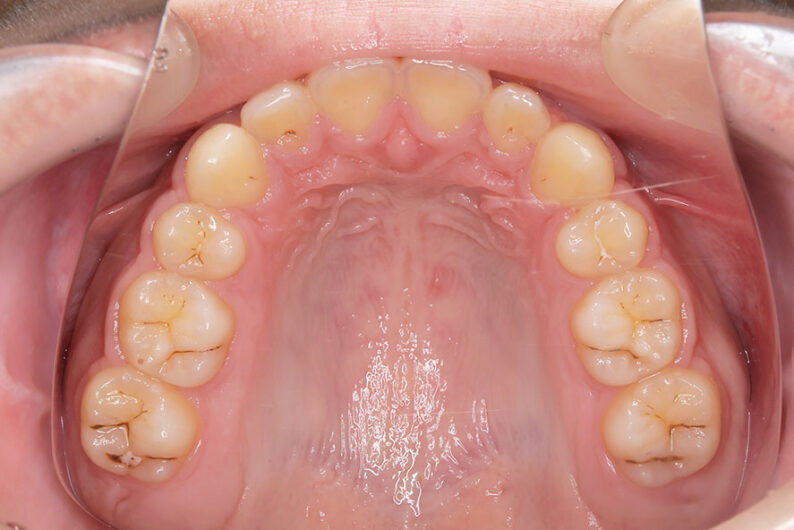

右上の前歯が生えてこない事を気にされ来院されました。 レントゲン写真から、上顎正中に過剰歯が埋伏していることが原因でしたので、抜歯して経過観察。 遅れて、無事に生えてきました。 もし、自然に生えてこない場合は、開窓して、引っぱり出します。(廷出) 状態により、引っぱり出せない場合もあります。 将来的にスペース不足により、上下顎前臼歯部に重度の叢生(がたつき)が予測できますので、がたつきを減らすために、小児矯正で側方拡大を行いました。 小児矯正で側方拡大を行ってもスペースが足りない場合(著しくスペース不足の場合)は、がたつき(叢生、八重歯)が残ります。 残ったがたつき(叢生)は、本格矯正ですべて生え変わった中学生から治せば問題ありません。 来院間隔が平均で1.5カ月でしたので半年ほど治療期間が長いです。